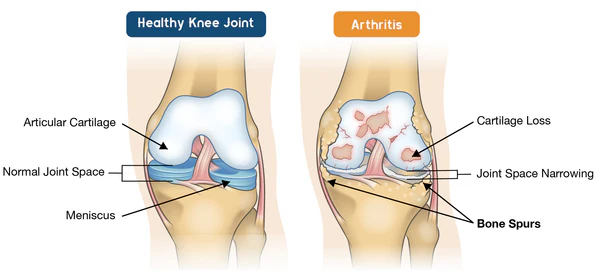

Bee venom is a poisonous fluid secreted by honey bees and has a variety of biologically active substances. The main component of bee venom is bee venom peptide, a kind of bioactive protein secreted from the acinar glands of honey bees, which has strong anti-inflammatory and analgesic effects, and can effectively relieve arthritis pain and swelling. When bee venom is applied to the skin, it may interact with the receptors involved in pain perception and inflammation. This interaction may lead to the modulation of inflammatory pathways, which may reduce the release of pro-inflammatory molecules that cause swelling of joints and bones.

- Relieves arthritis pain

- Eliminates joint inflammation Eliminates cysts and swellings

- Promotes joint tissue repair Improves joint flexibility and mobility

- Promote joint repair and regeneration